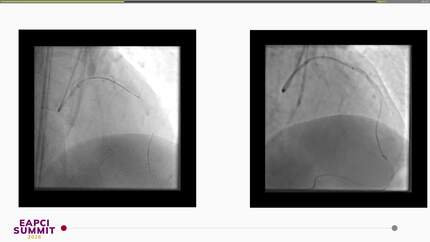

Snaring a protruding aorto-ostial coronary stent: A novel anchoring technique for facilitating antegrade treatment of a chronic total occlusion